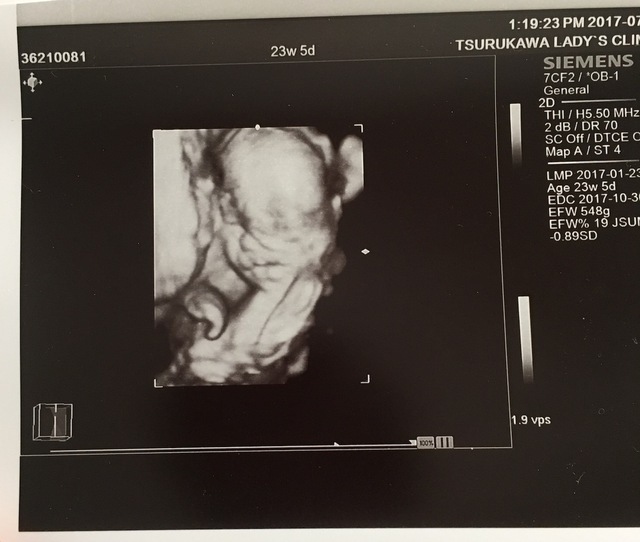

23週5日(23w5d・男の子)|とみとみ さん(29歳)

エコー写真撮影時のエピソード:

初めてエコー写真を見た時、このマメのようなものが人間になるの?と不思議な気持ちになりました。主人もこれ?と実感がわかない様子でしたが、月日が経つにつれて人間らしい姿になってくことに感動!

家族にも毎回エコー写真を送り成長を見てもらっていますが、すごーい、神秘だよねと毎回みんなで感動しています。